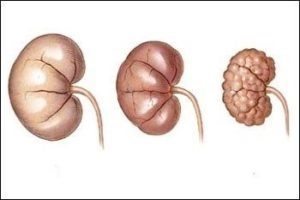

Cu o creștere lentă în oncologie, tumora va acoperi toată zona mare a corpului. Prin urmare dimensiuni Neoplasm va crește. Cu cat mai mare zona, cu atât mai mare ficatul nu reușește.

În plus, adenomul se dezvoltă în același mod ca și carcinomul cu celule, atât de mulți experți medicali sugerează că aceasta este o stare precanceroasă. Prin urmare, un sfat, primele semne de boală consultați imediat un medic pentru ajutor.